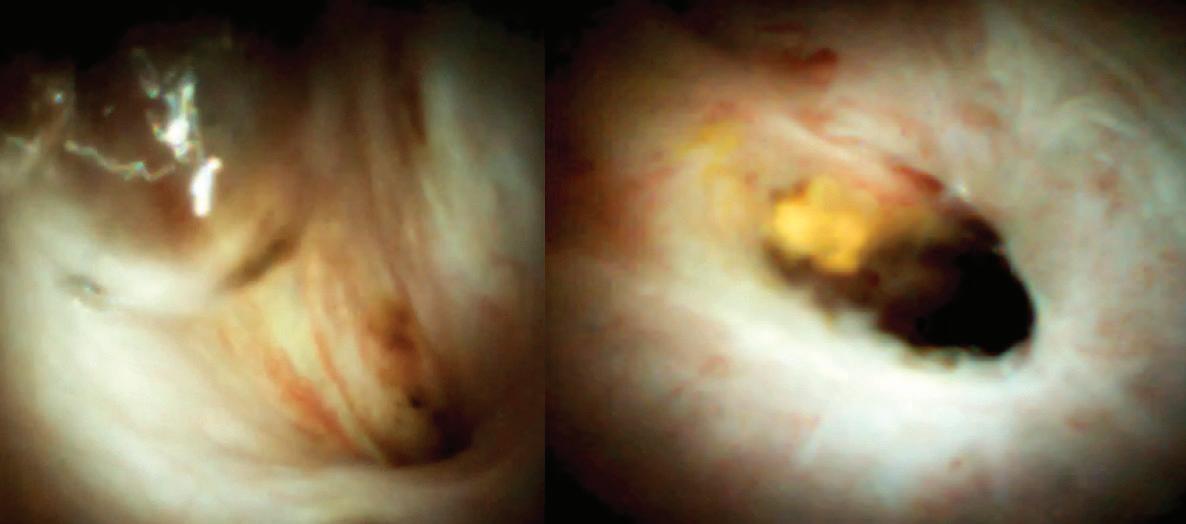

като приложение то им за дренаж на псевдокисти остава спорно, предимства та им при WON са до казани. Според меж дународен консенсус LAMS са най-подхо дящите стентове за дренаж на WON с ре дица преимущества пред пластмасови те стентове[8]. Спо ред данни от големи проучвания, LAMS са с доказани пре димства пред пласт масовите стентове при дренаж на WON, докато при псевдо кисти трябва да се имат предвид спе цифичните усложне ния, свързани с при ложението им[9] (Фиг. 3-5).

Фиг. 3

Трансгастрална позиция на LAMS при дренаж на некротична колекця- ен досонографски

и ендос копски аспект Фиг. 2 Стент със специален ди зайн Hot AXIOS (Boston Scientific Corp.) Фиг. 4 Ендоскопски аспект на некротичната колекция Фиг. 5 Компютърна томогра фия, демонстрираща пълно обратно развитие на некротична колекция след поставяне на транс гастрален стент ради което рискът от ликидж, билиарен перитонит или раз витие на други фа тални компликации е значимо по-висок.